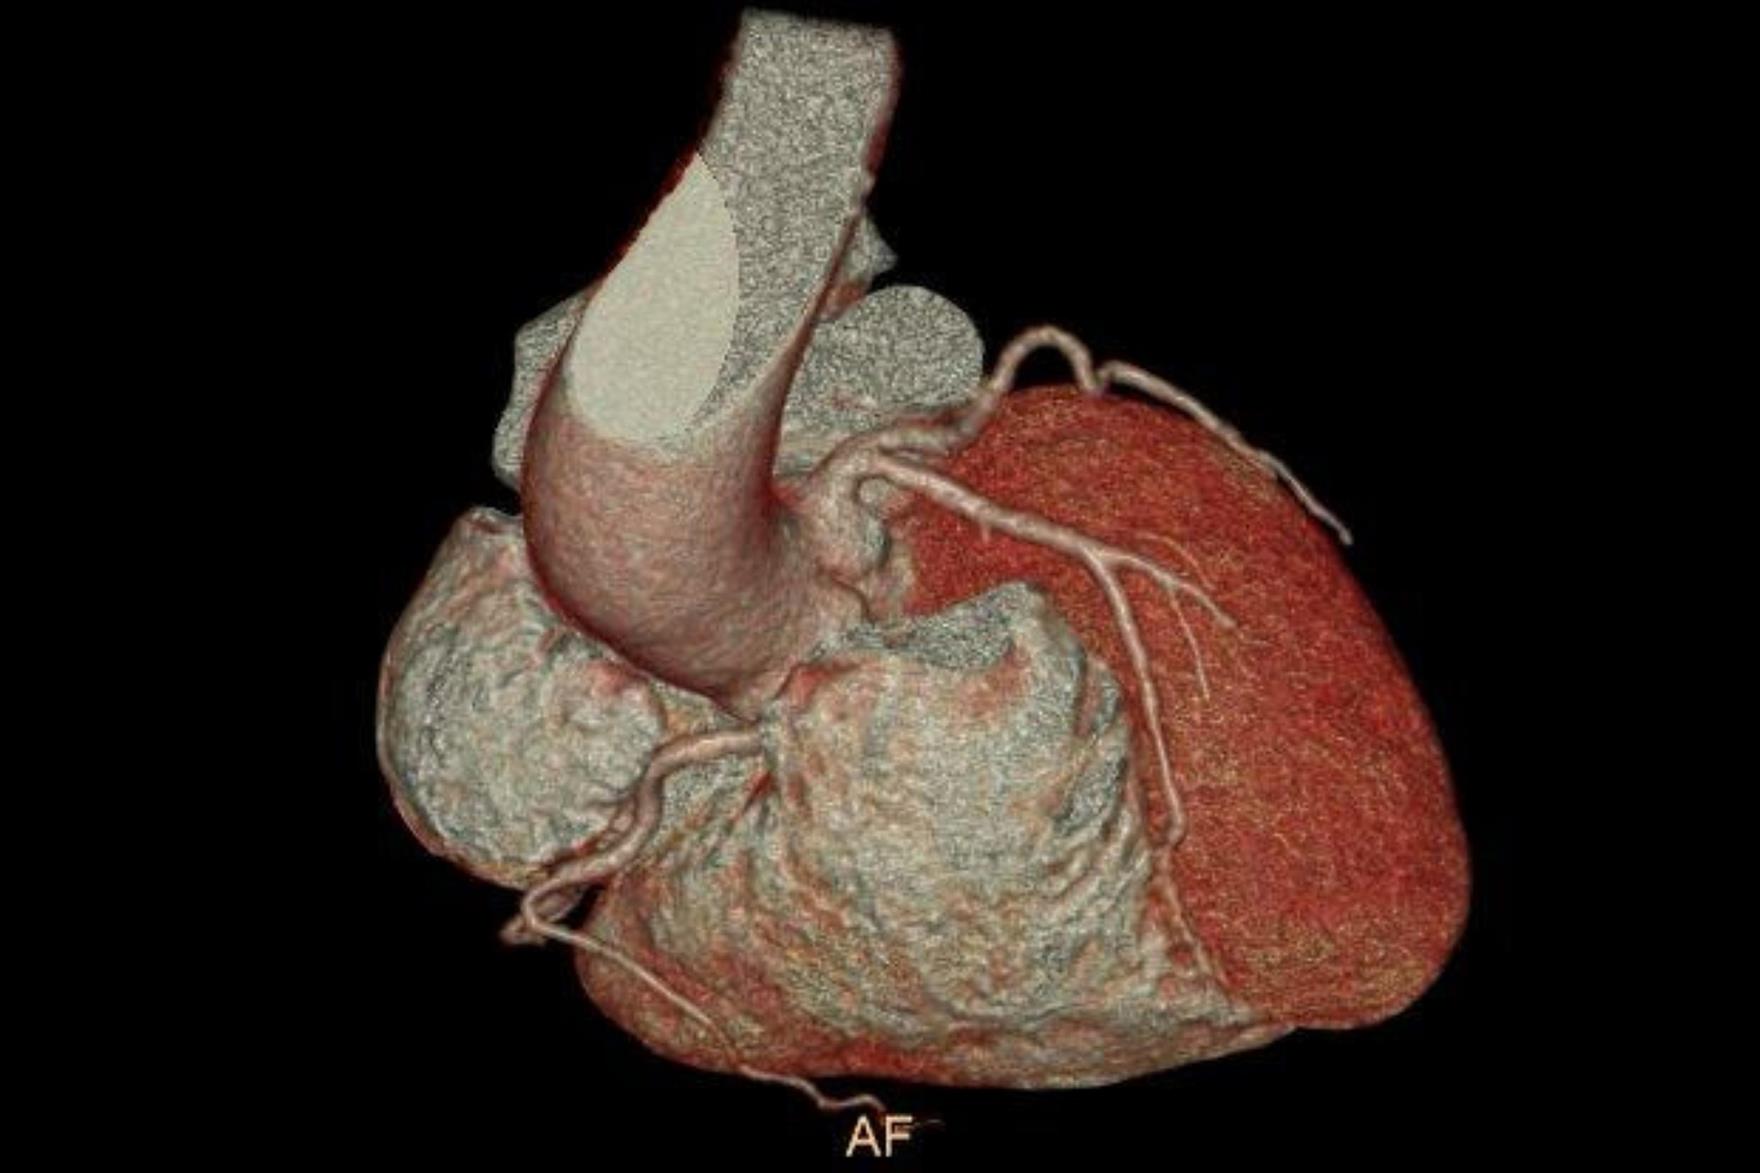

PAÜ Hastaneleri Radyoloji Anabilim Dalı Öğretim Üyesi Doç. Dr. Vefa Çakmak yaptığı açıklama da şunları söyledi: “Pandemi döneminde hayatımıza daha sık giren bilgisayarlı tomografi (BT), günümüzde tanı ve tedavi süreçlerinde hayati önem taşıyan bir görüntüleme yöntemi olarak kullanılmaya devam ediyor. Radyasyon içeren bu teknoloji, pek çok organın ayrıntılı şekilde incelenmesini sağlarken, acil durumlarda hızlı teşhis imkânı sunarak hayat kurtarıcı bir rol üstleniyor. Özellikle kanserin tanı ve takibinde, trafik kazaları, beyin kanamaları, kırıklar ve büyük cerrahiler öncesinde önemli bir yer tutuyor. BT ile kalbi besleyen damarların detaylı şekilde görüntülenmesi mümkün hale geliyor. Halk arasında ‘sanal anjiyo’ olarak bilinen bu yöntemle, kalpte işlem gerektiren damar tıkanıklıkları erkenden saptanabiliyor. Böylece hastalar, gereksiz klasik anjiyo işlemlerinden korunuyor. Aynı anda kalp duvarları, kalp içindeki pıhtı ya da tümör gibi oluşumlar ve ritim bozukluğuna neden olabilecek yapılar da değerlendirilebiliyor. Ayrıca, bu çekimler sırasında düşük dozla akciğer görüntülemesi de yapılarak yapısal akciğer hastalıkları, akciğer kanserleri ve göğüs kafesiyle ilgili kemik problemleri de tespit edilebiliyor. Çekim öncesinde hastanın böbrek fonksiyonlarını korumak amacıyla kreatin ve GFR gibi kan testleri yapılıyor. Hastanın mevcut hastalık öyküsü ve ilaç alerjileri sorgulanıyor. Kaliteli bir görüntü elde edebilmek için kalp atım hızının dakikada 70 civarına düşürülmesi gerekebiliyor; bu durumda nabız düzenleyici ilaçlar kullanılabiliyor. İşlem sırasında hasta monitörize ediliyor, göğüs bölgesindeki metal eşyalar çıkarılıyor ve yaklaşık 10–15 saniyelik nefes tutması isteniyor. Kardiyak BT çekimi 4–10 saniye sürüyor ve görüntülerin değerlendirilip raporlanması genellikle aynı gün içinde tamamlanıyor.”